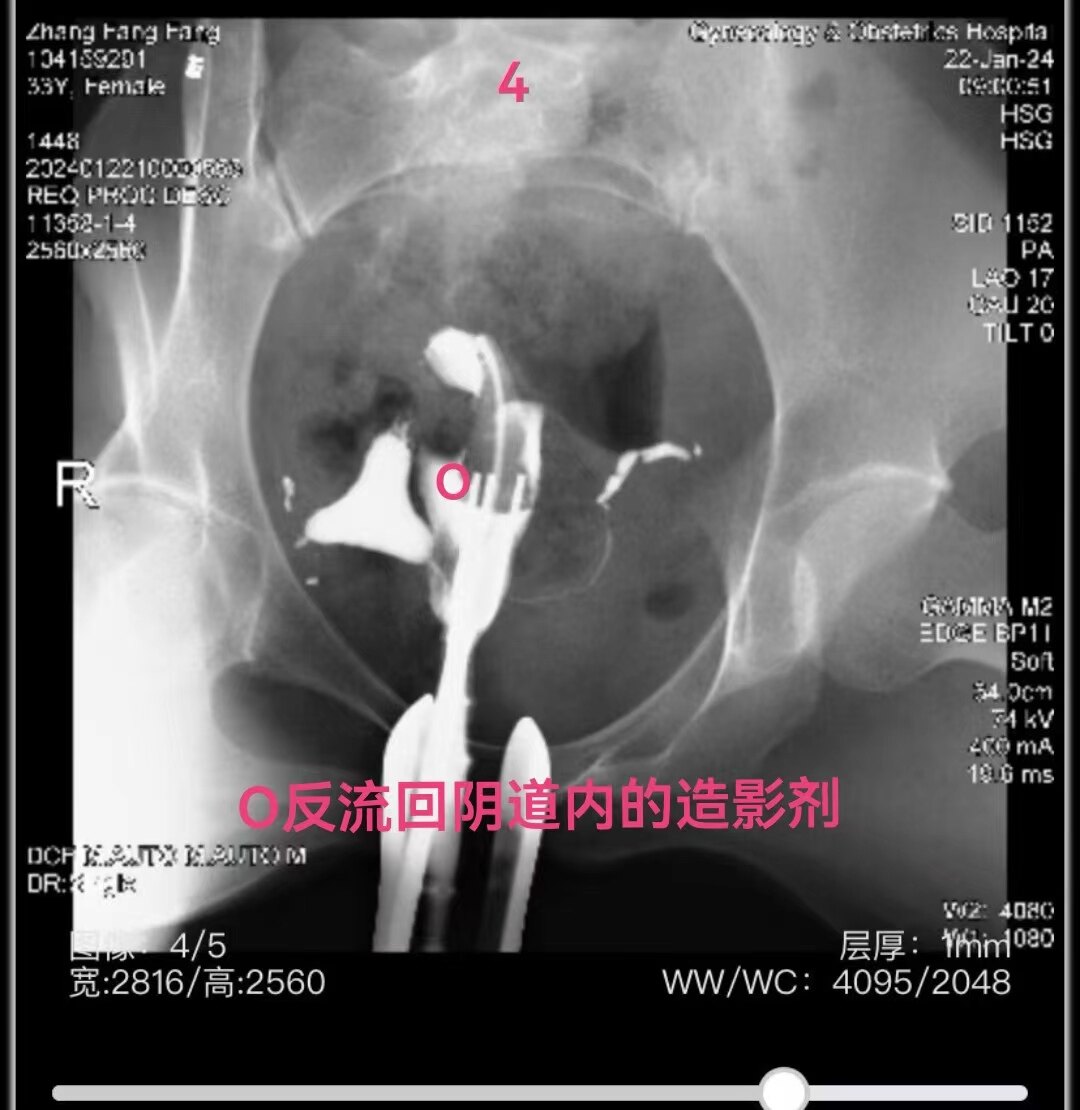

左侧输卵管显影至伞部,右侧输卵管显影至壶腹部近段。造影剂返回到阴道

4.jpg